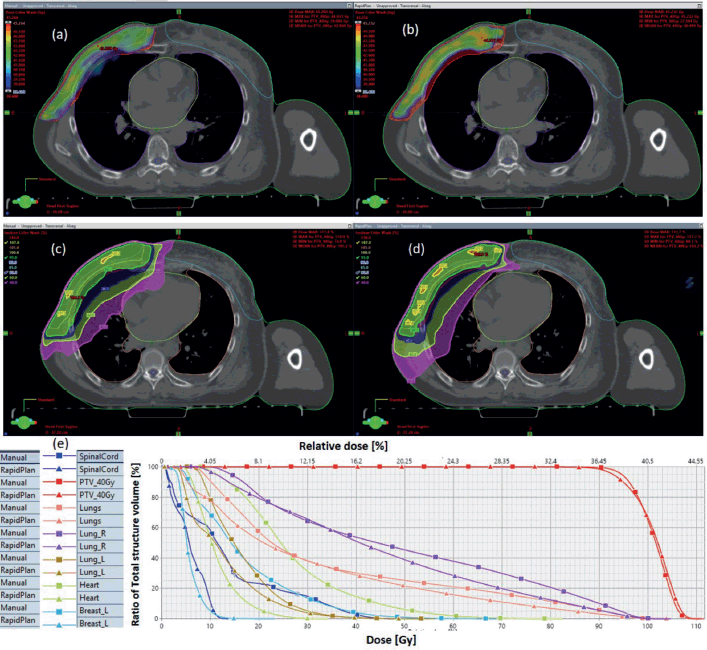

Figure S1 shows a representative breast plan, comparing VAPs and VMPs dose distributions and corresponding DVHs.

Figure S1. Typical right breast plan, comparing: (a) 95% of PTV40.5 for VMP, (b) 95% of PTV40.5 for VAP, (c) colour wash – PTV40.5 for VMP, (d) colour wash – PTV40.5 for VAP and (e) DVH for VMP versus VAP showing the PTVs and OARs.

Results indicate that both computation methods achieve very good PTV coverage and OAR sparing, with VAPs showing superior protection of contralateral breast and spinal code (Figure S1).

Figure S2a,b and c compare the box-and-whisker plots for OARs for breast and rectum, cancer sites, respectively. Statistically significant differences were observed in the breast cases for heart, contra lung, and spinal code. Statistically significant differences were observed in the breast cases for heart, contra lung, and spinal code. A similar tendency is observed for the rectal plans (Figure S2b and c), where both VAP and VMP methods failed to achieve the bladder: V40Gy ≤ 40% and femoral heads: Dmax ≤ 50 Gy, failing for VAPs.